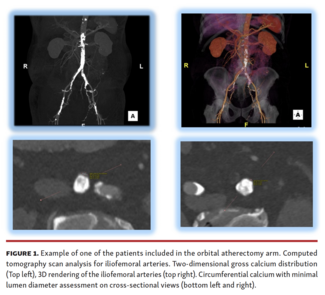

Cezar S. Staniloae, MD; Homam Ibrahim, MD; Jorge Fuentes, MD; Carlos Gonzales, MD; Anna Kapitman; Hasan Jilaihawi, MBChB, MD; Samantha Vidal, MS; Sonja Paschke, MD; Kazuhiro Hisamoto, MD; Mathew Williams, MD

The use of orbital atherectomy to prepare iliofemoral vessels for large-bore access prior to TAVR is discussed.